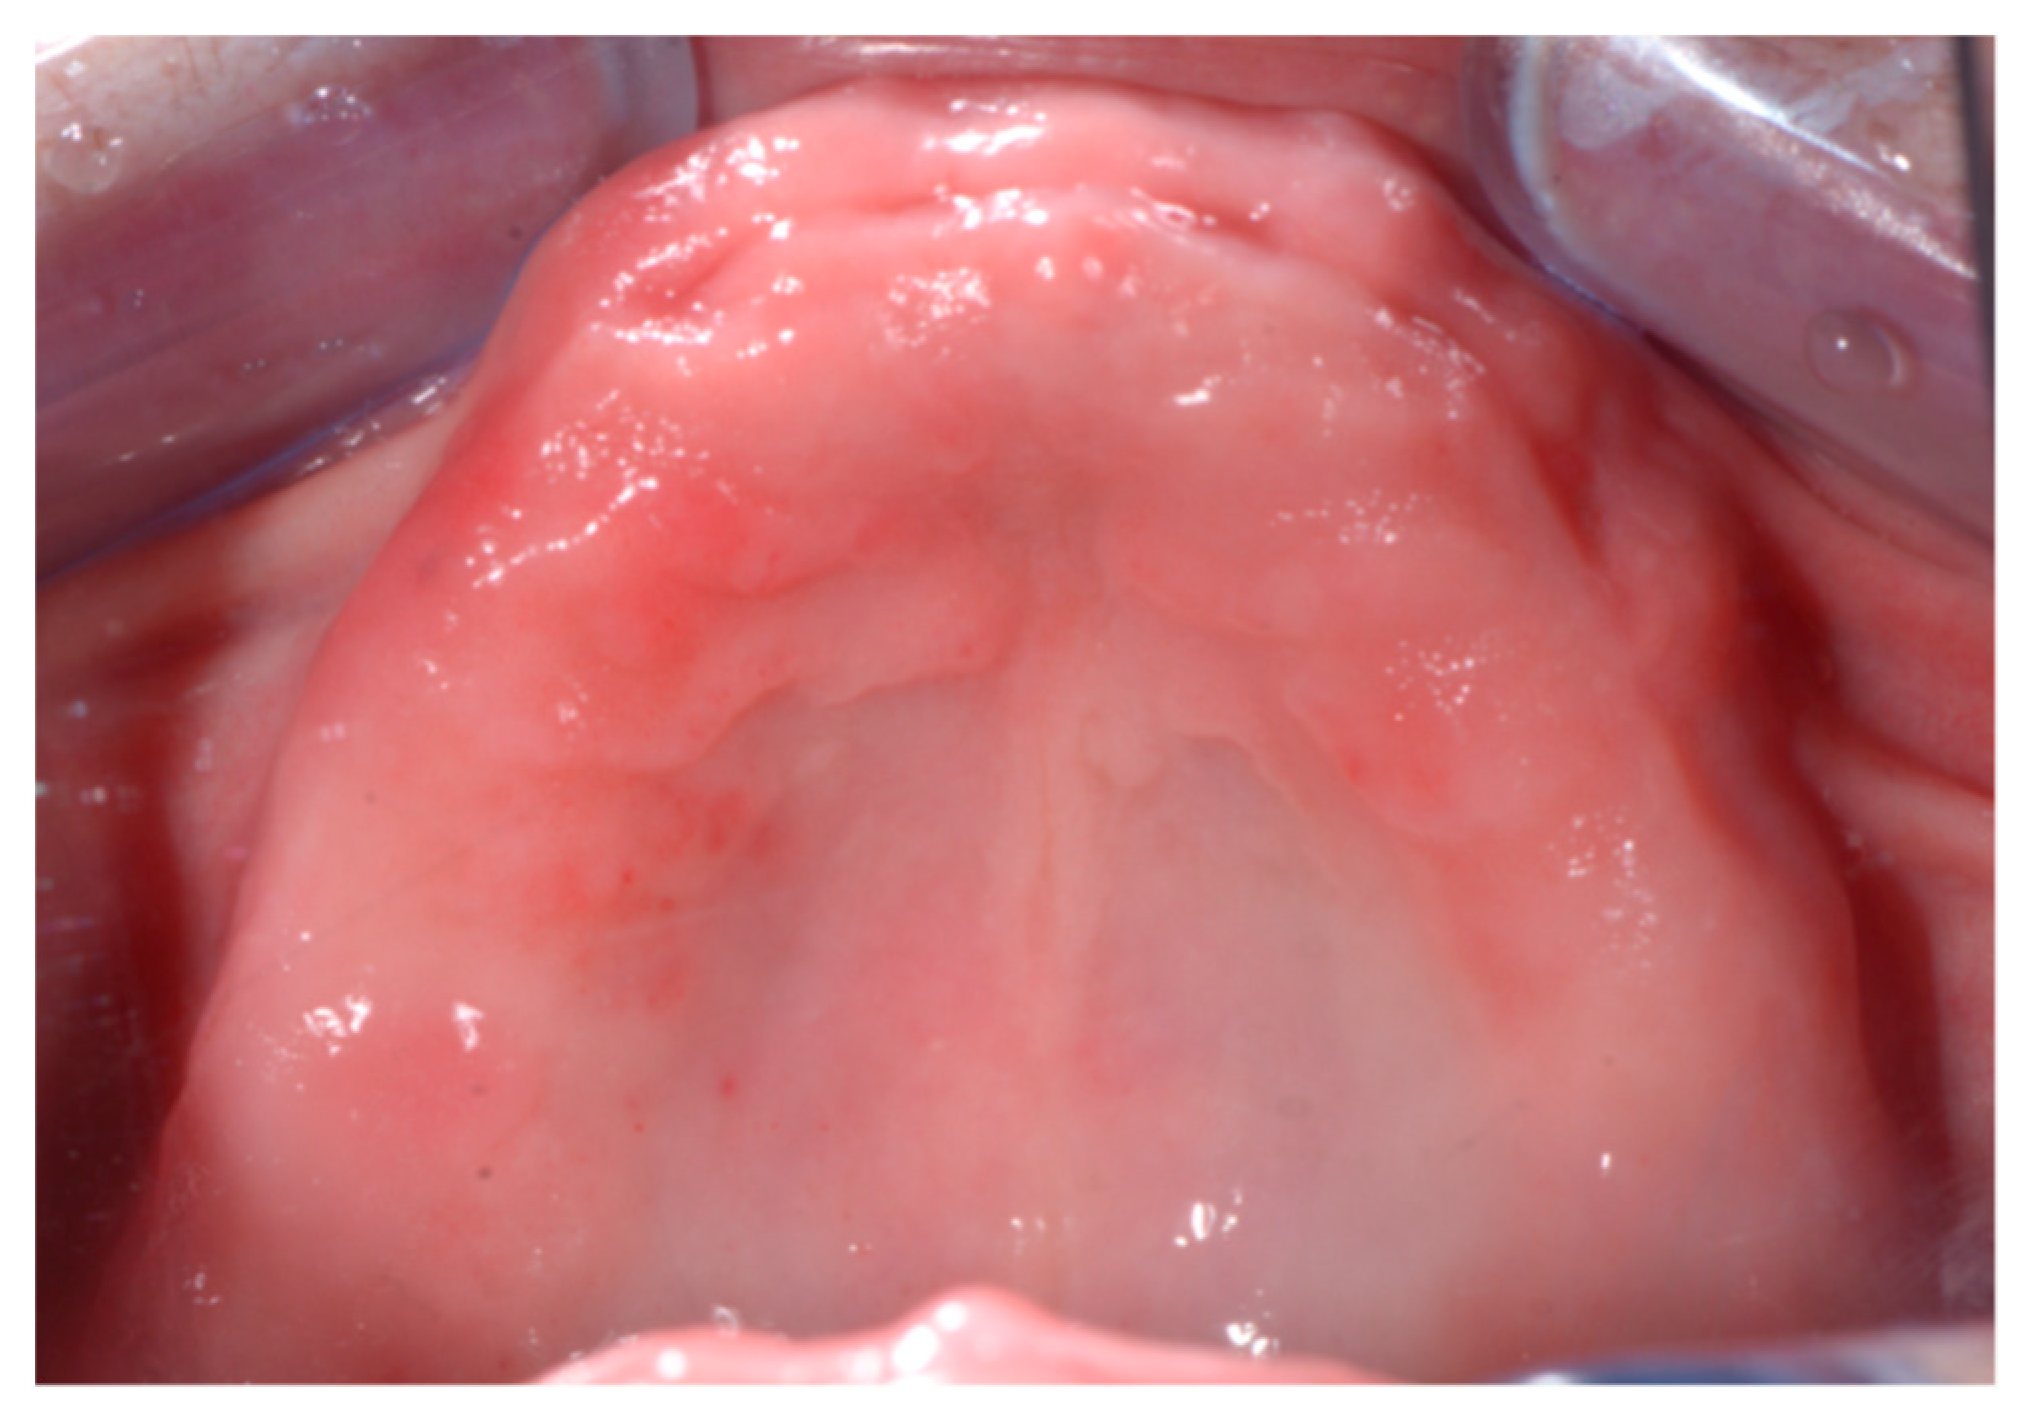

2.2. Clinical Procedure

2.2.1. First Appointment

2.2.3. Third Appointment (Traditional Protocol)

2.2.4. Fourth Appointment (Traditional Protocol): Surgical Phase and Immediate Loading Prosthesis